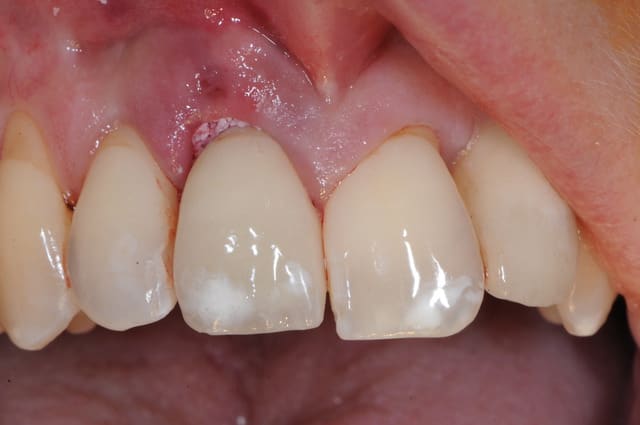

Je poste le cas en avant premiere ici.

C'est tout frais du mois dernier.

beau travail, mais

les 2 cas ne me semblent pas comparable dans la mesure ou tu as réussi à préserver un bandeau d'os vestibulaire presque au niveau des collets. Il permet un effet piquet de tente incomparable et évite les mauvaises surprises de perte importante de volume de biomat a la cicatrisation.

Dans l'autre cas la table vestibulaire est manquante, le résultat d'une EII beaucoup moins prévisible et dans un secteur esthétique j'aime pas jouer a la roulette russe.